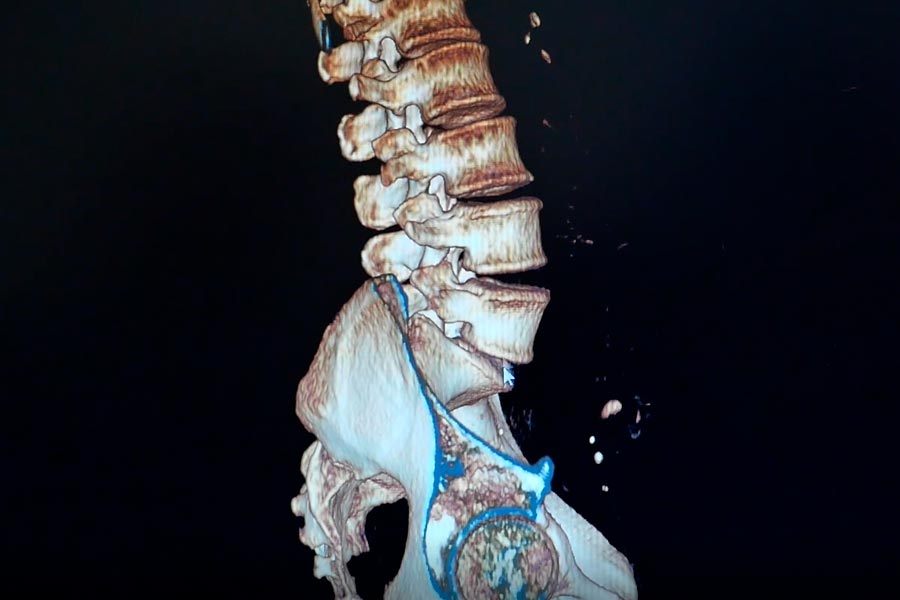

Caso clínico: endoscopia de columna multinivel L4L5 y L5S1

Los síntomas que presentaba el paciente eran dolores acentuados en las piernas, claudicación a la marcha y calambres y hormigueos en las piernas.

Durante la intervención quirúrgica, se abordarán los dos niveles mediante la técnica de endoscopia de columna.